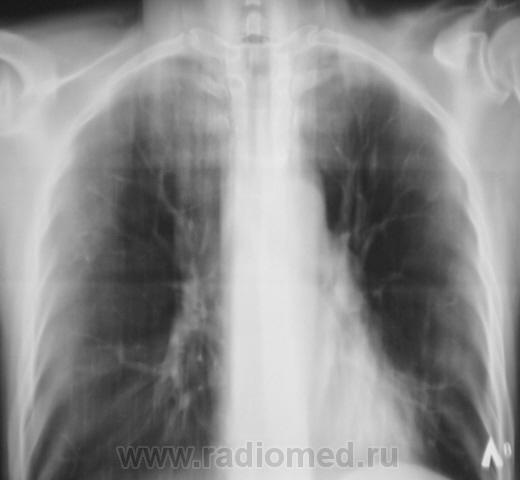

Следущий "контроль".

Следущий контроль (сегодня).

После лечения динамика очень хорошая.

А сейчас, если не ошибаюсь, есть свежие очаги слева?

Я тоже отметил "свежие" очаги, но они появились на "фоне" курса лечения.

Мы трактовали это как крупноочаговые тени.

У фтизиатров лечение, у них, родимых.